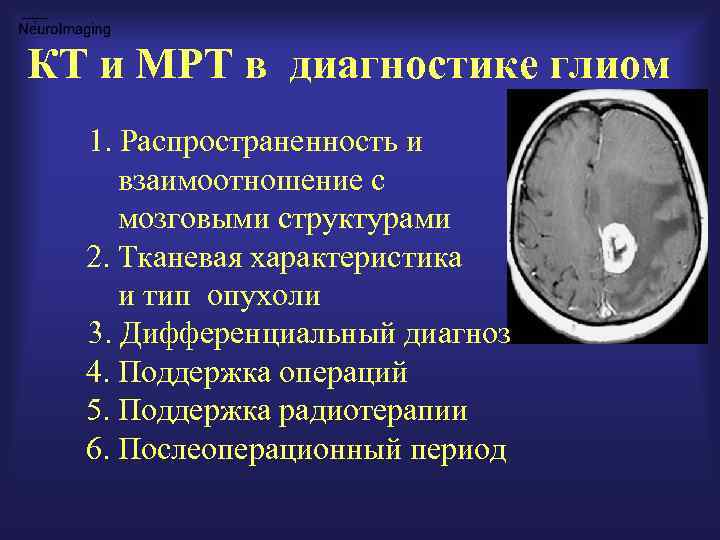

КТ и МРТ в диагностике глиом 1. Распространенность и взаимоотношение с мозговыми структурами 2. Тканевая характеристика и тип опухоли 3. Дифференциальный диагноз 4. Поддержка операций 5. Поддержка радиотерапии 6. Послеоперационный период